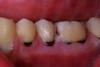

(2.) Lingual and facial maxillary views of 5-year-old patient, 1 year after caries attenuation with SDF. The parents were not concerned about the black staining.

Figure 2

(3.) Lingual and facial maxillary views of 5-year-old patient, 1 year after caries attenuation with SDF. The parents were not concerned about the black staining.

Figure 3